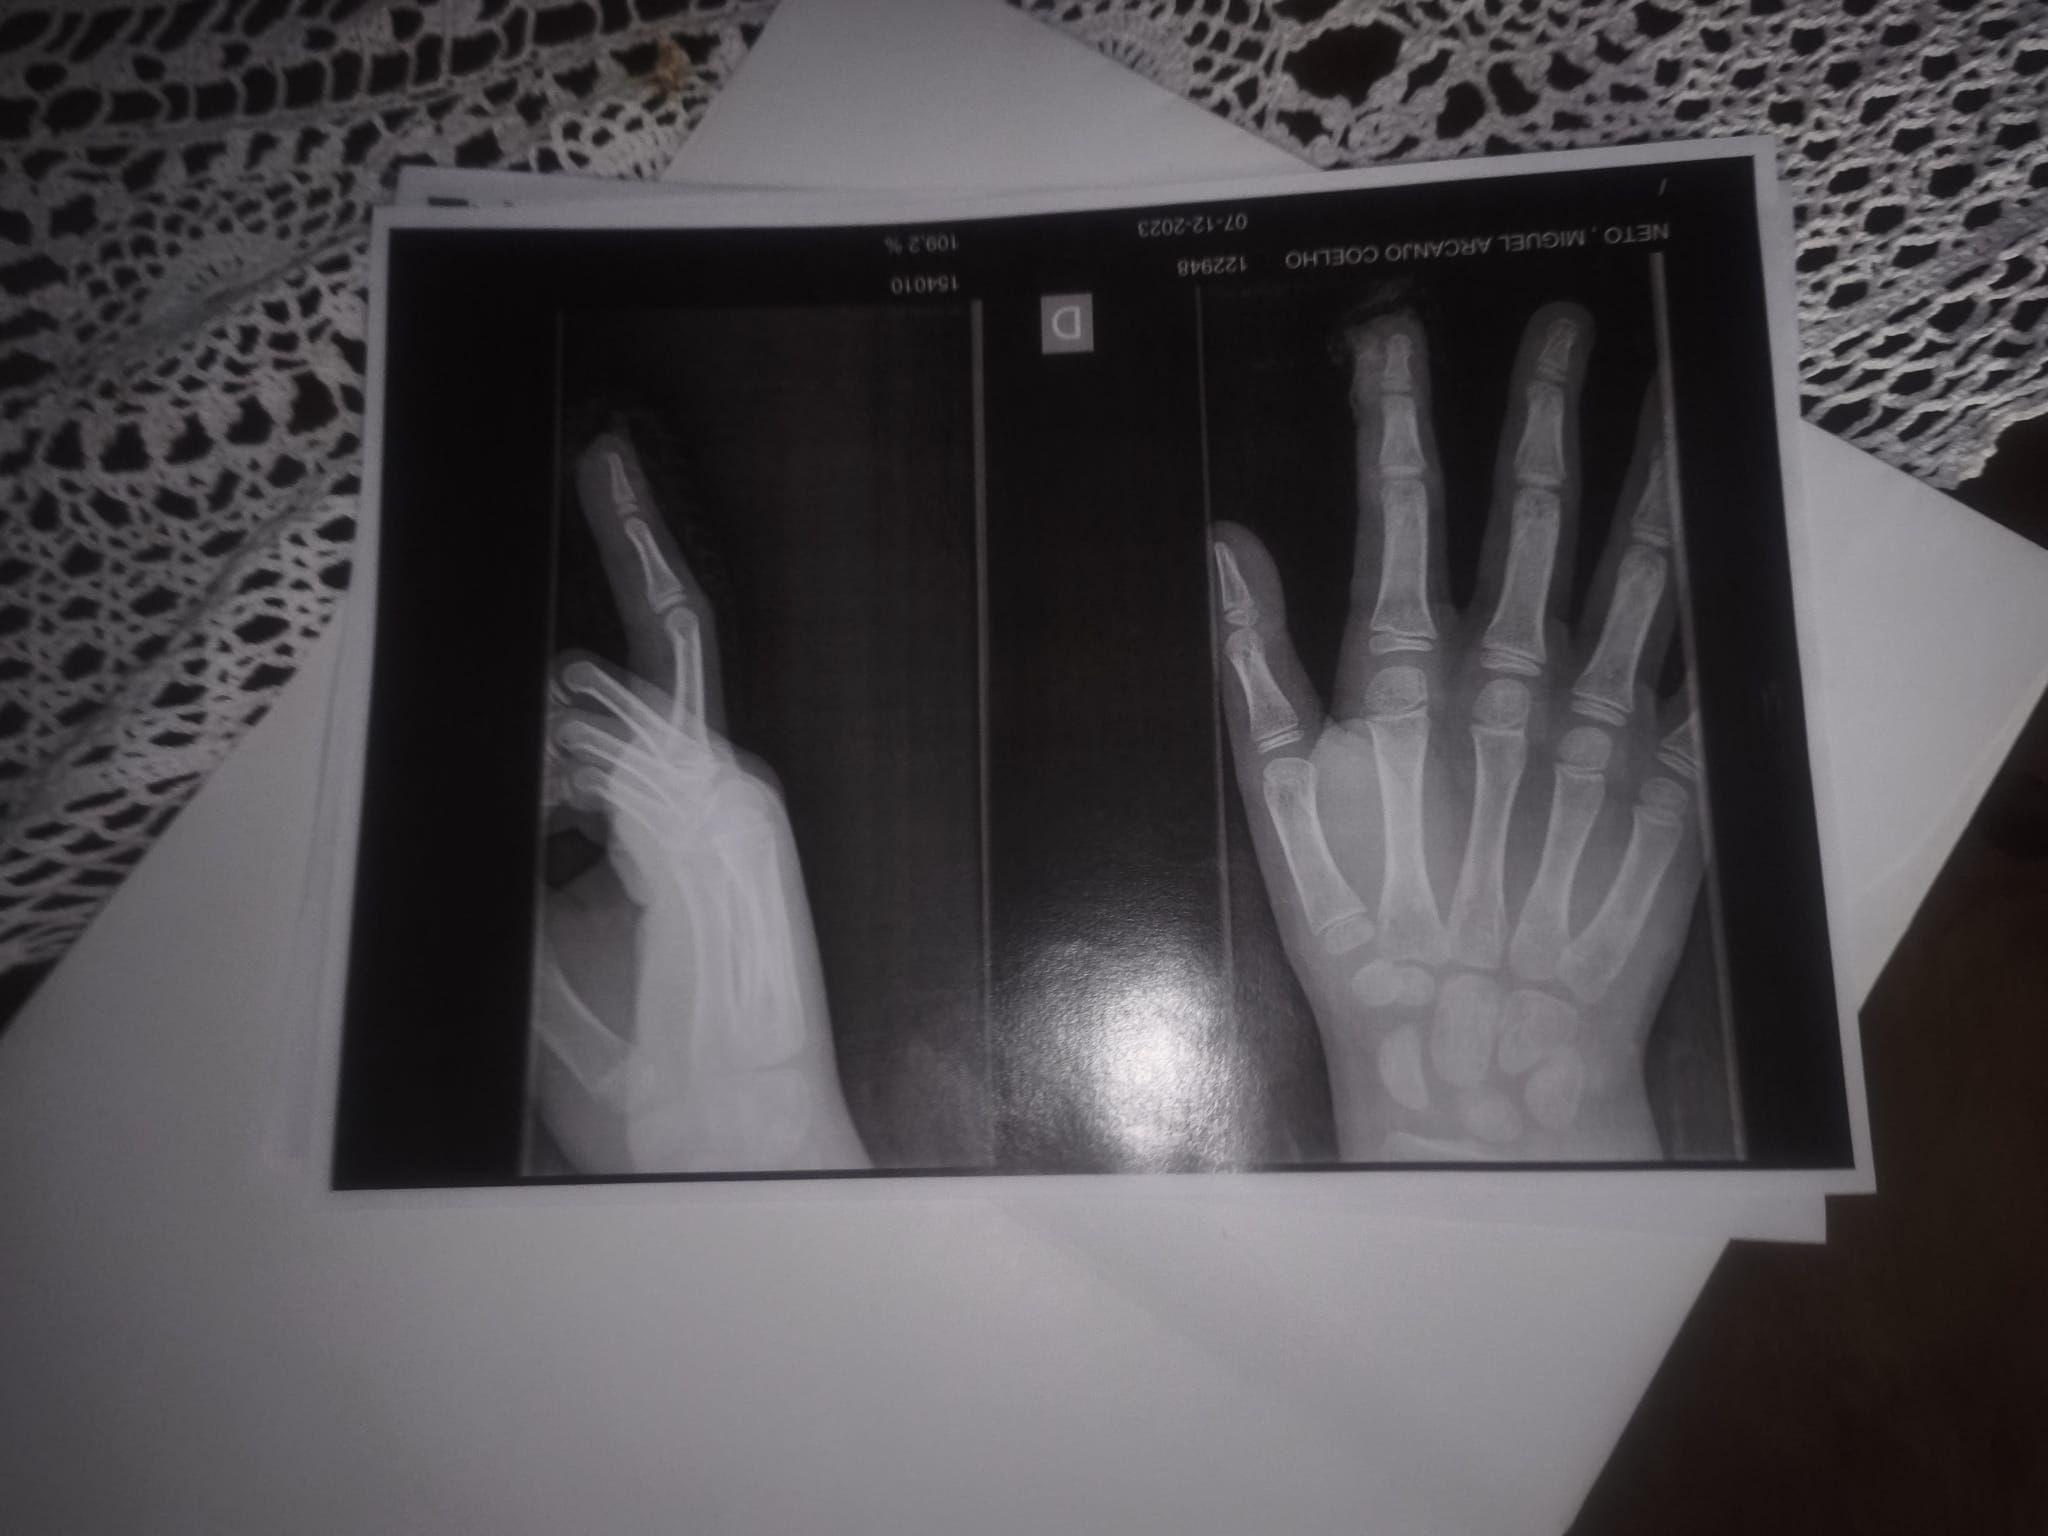

No hospital, José passou por três horas de cirurgia, mas não foi possível reconstituir as pontas dos dois dedos amputados.

Apenas após acordar, o menino conseguiu relatar à família o que havia acontecido.

Segundo José, duas crianças o encurralaram no banheiro e fecharam a porta de uma das cabines em sua mão. Preso, ele teve que passar pelo vão abaixo da porta para pedir socorro.